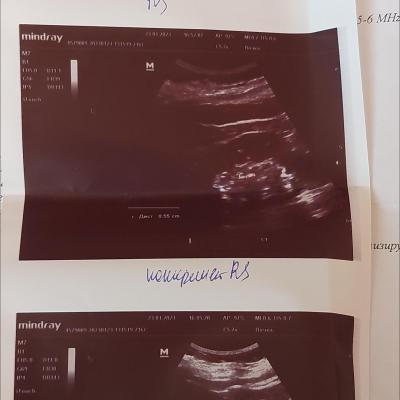

Добрый день. По УЗИ обнаружены 2 камушка 5-6 мм и уролог назначил 3 препарата Роватинекс, Блемарен и Цистон. Я почитала и вроде как поняла , что первые 2 препарата, это практически одно и то же, ещё и дорогущее. Могут они выйти от Роватинекса, тем более его пить надо 3 месяца, а потом ещё Блемарен 3 месяца и цистон столько же.